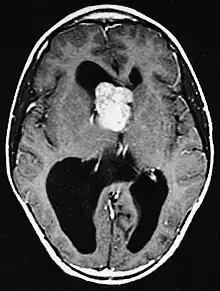

MRI of brain with sub-ependymal giant cell astrocytoma

Diagnosis is made by imaging with a contrast-enhanced MRI or CT scan of the brain.